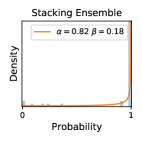

5.1 Distribution of Uncertainty Scores

Distribution of Uncertainty Scores Across Different Severity Levels As explained in Section 3, each uncertainty metric essentially defines an order/ranking among the data points. We conducted an analysis to better understand what data will be assigned high uncertainty under a particular uncertainty metric . Picking out the highest ranked data points (), we calculated the ratio of data points from each SL. Figure 4 summarizes the results as box plots for the Kaggle-DR and the Messidor-2 datasets; additional detailed statistics can be found in Table S.1 in the supplementary materials. From the plot and table, SL1 & SL2 examples account for a higher proportion among the top-ranked uncertain examples across the three ensemble methods. This finding matches our intuition that incipient disease examples (SL1 & SL2) are more likely to be considered uncertain by ensemble methods due to their ambiguity.

Comparing the three ensemble methods in Figure 4, the stacking ensemble method has the highest ratios of SL1 & SL2 data among the high-uncertainty examples it identified under both mean and var. TTA showed slightly better performance than MC-dropout but still falls behind the stacking ensemble method. Considering the fact that SL0 examples accounted for the majority of the dataset, the stacking ensemble method was much more precise (specific) in selecting truly ambiguous data points that were difficult to classify. From Figure 3, we can also see that the stacking ensemble method greatly outperformed the other two methods in finding false negatives under both mean and var uncertainty metrics.

In contrast, the MC-dropout method showed the worst overall performance among the three, as it can be seen from the high ratios of SL0 examples among the uncertain negatives in Figure 4. The histograms in Figure 2 provides another perspective to look into the phenomenon, where a decent proportion of MC-dropout model’s predictions on SL0 inputs entailed low confidence (far from 0 or 1), which from another angle explained why MC-dropout was less specific in terms of lower FNP; many no-DR inputs (i.e. SL0) were erroneously assigned high uncertainty by MC-dropout models.

It is still an open question why the evaluated MC-dropout networks signaled relatively high uncertainty on SL0 & SL3 & SL4 data that are less likely to be ambiguous. We conjecture that much of the “uncertainty” indicated by disagreement among test-time dropout samples actually reflects the stochastic nature of dropout networks rather than the real decision uncertainty associated with the data. It is worth noting that the MC-dropout model we evaluated was not weak per se; they all achieved above Area Under Curve (AUC) scores on test sets. The weakness of individual test-time samples (which explains their low-confidence predictions on SL0 & SL3 & SL4) might have been hidden when they are aggregated into an ensemble—a well-known advantage of ensemble learning. Our results suggested that the uncertainty information given by implicit ensemble methods such as MC-dropout and TTA might not be as reliable as that from explicit ensemble approaches (e.g., stacking ensembles). Similar findings on MC-dropout can be found in some previous papers [1].